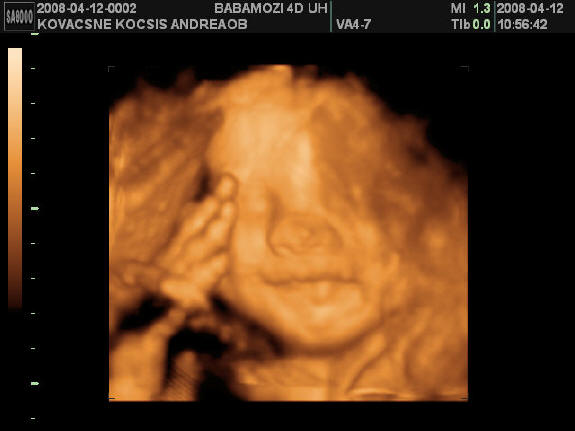

2008.04.12 10:53